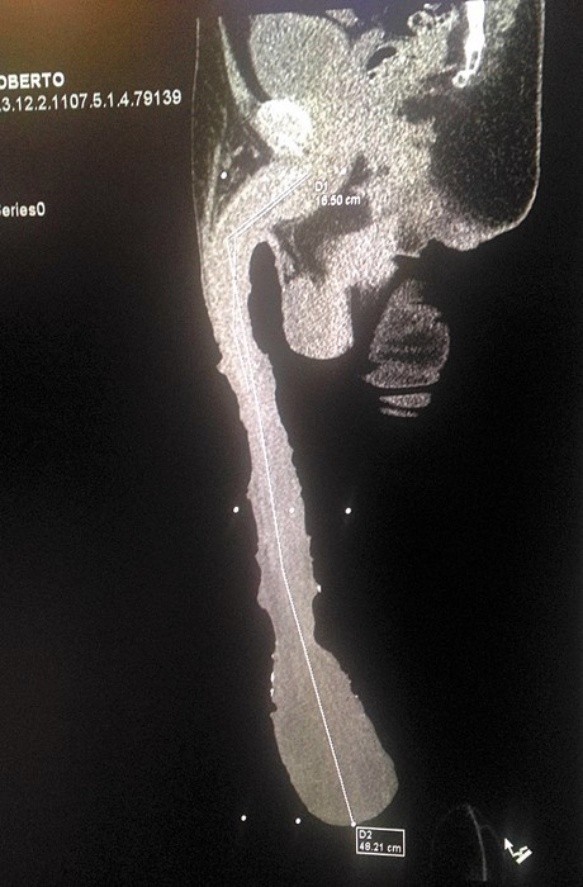

Una tomografía en 3D descarta que el mexicano use prótesis u otro tipo de trucos. El hombre es tratado hace meses en un centro de salud de Saltillo, Coahuila. Allí se determinó que deberán realizarle más exámenes para conocer la causa del crecimiento del miembro.

Roberto Esquivel Cabrera cubre los 48,2 centímetros de virilidad con gasas y telas. Y, literalmente, le llega hasta el tobillo.